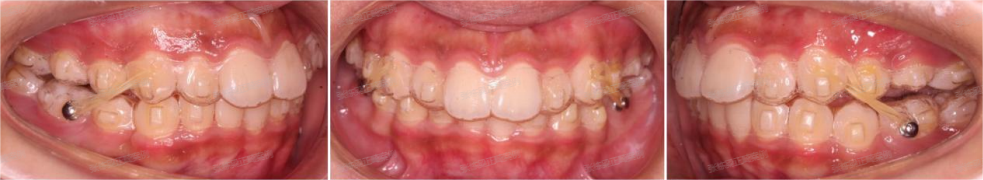

这位小朋友主诉牙不齐,嘴突,没下巴,来面诊时刚刚结束替牙期,正处于年轻恒牙列,生长发育高峰期。

根据牙片资料和口内检查发现骨性,上前牙唇倾,lll度深覆盖,上下颌牙弓狭窄,右下4左下5先天缺失,上颌轻度拥挤,下颌牙齿散在间隙,颏唇沟较深,闭唇时颏肌紧张。

可以看到佩戴4个月的时候,孩子的牙齿和面型有了不错的变化,上下颌牙套贴合,双侧兔子皮筋二类牵引佩戴良好。